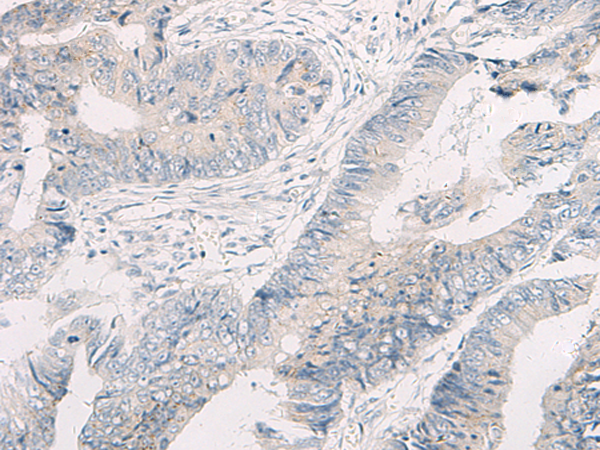

分类: 科研抗体货号: P12418别名: T1A; GP36; GP40; Gp38; OTS8; T1A2; TI1A; T1A-2; AGGRUS; HT1A-1; PA2.26应用: WB,IHC反应种属: Human